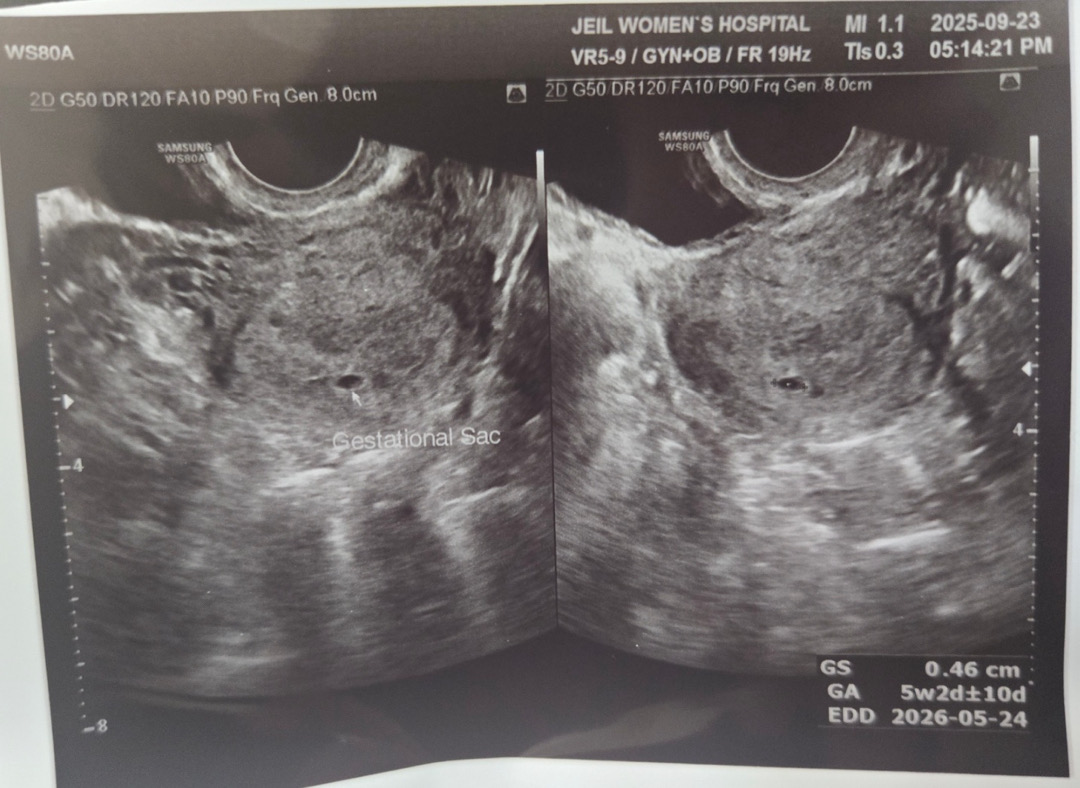

5주2일차 초음파

9/23(화)에 5주 2일차, 처음으로 아기집 확인했어요. 아직 아기집도 너무 작고.. 난황도 안 보여서 아직 걱정이 되는데요.. 병원에서는 2주 뒤에 오라고 하시는데 추석 연휴가 껴서요.. 언제쯤 병원 방문하면 좋을까요ㅠㅠ